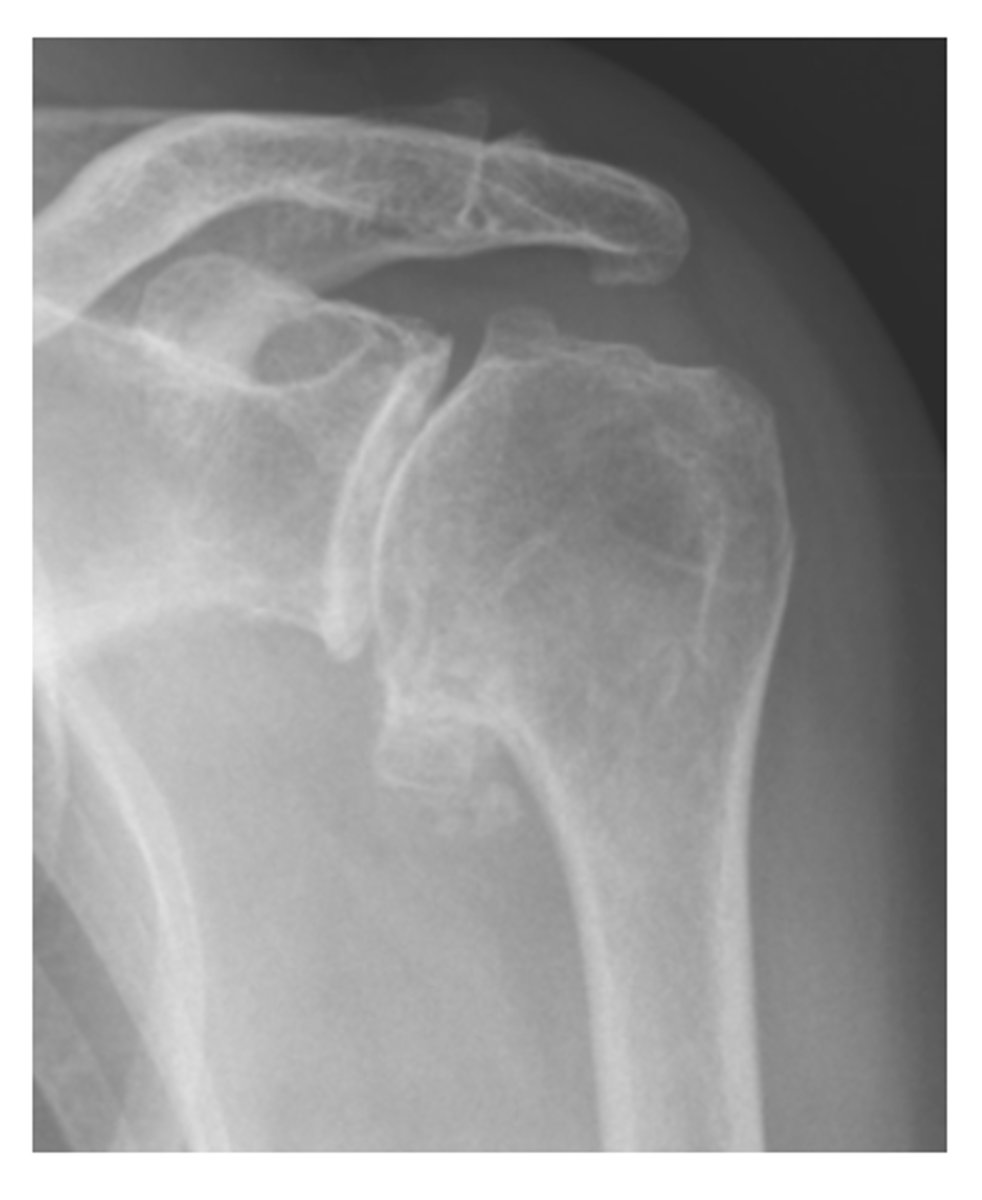

what are the three indications for hip radiograph

hip pain

avascular necrosis

stress fractures